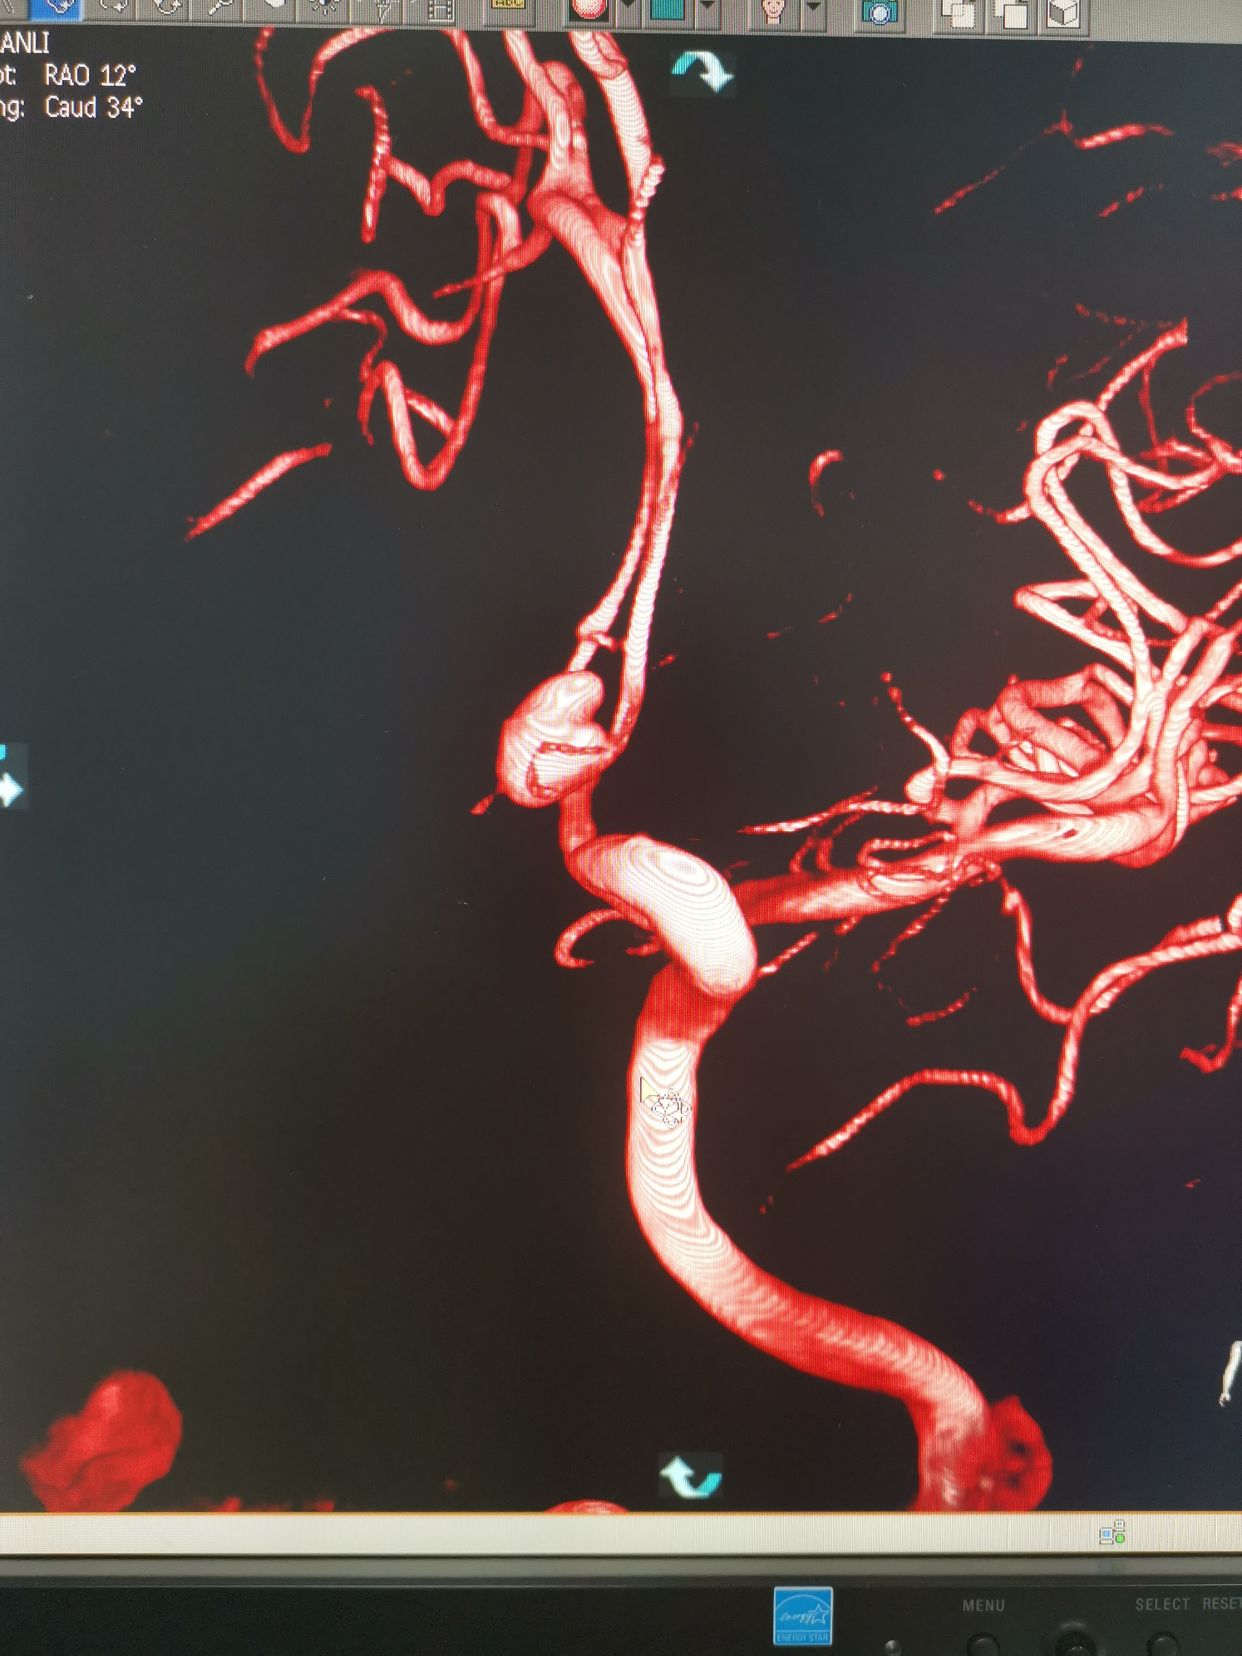

造影过程中,患者出现意识障碍加深,烦躁,不能配合,考虑颅内出的增加可能。术中请麻醉科老师急诊行气管插管麻醉。后行左侧颈内动脉3D造影。

左侧颈内动脉3D